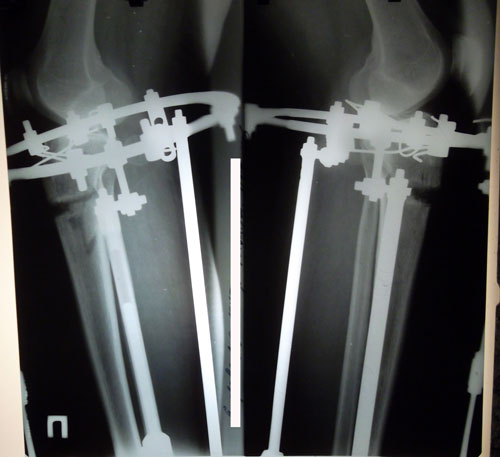

30 дней с момента операции.

РЕНТГЕН НА 30 - ЫЙ ДЕНЬ С МОМЕНТА ОПЕРАЦИИ.

РЕНТГЕН ДО ОПЕРАЦИИ

Рентген в 121 день. Снимать аппараты рановато, ждём ещё месяц. Делаем повторный рентген и смотрим. Можно снимать не 10 апреля, а на несколько дней раньше. кушайте творог, мясо, кальций, холодец, мумиё (как учили в клинике) и позитивное настроение! 04000000.

Рентген перед снятием аппаратов.

в аппаратах пред снятием.